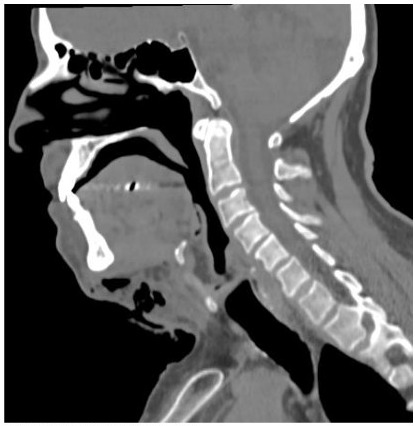

Um paciente de 55 anos, sexo masculino, apresentando quadro de infecção odontogênica complexa que ganhou espaços fasciais secundários foi internado em unidade hospitalar de emergência. Após Tomografia Computadorizada, foi observado em um corte sagital mediano a seguinte imagem. Ao analisá-la, assinale os itens abaixo.

I. O espaço submandibular encontra-se acometido e é observado na imagem.

II. A infecção envolve o espaço mediastinal.

III. O espaço pré-vertebral encontra-se acometido em nível da vértebra Cervical C3.